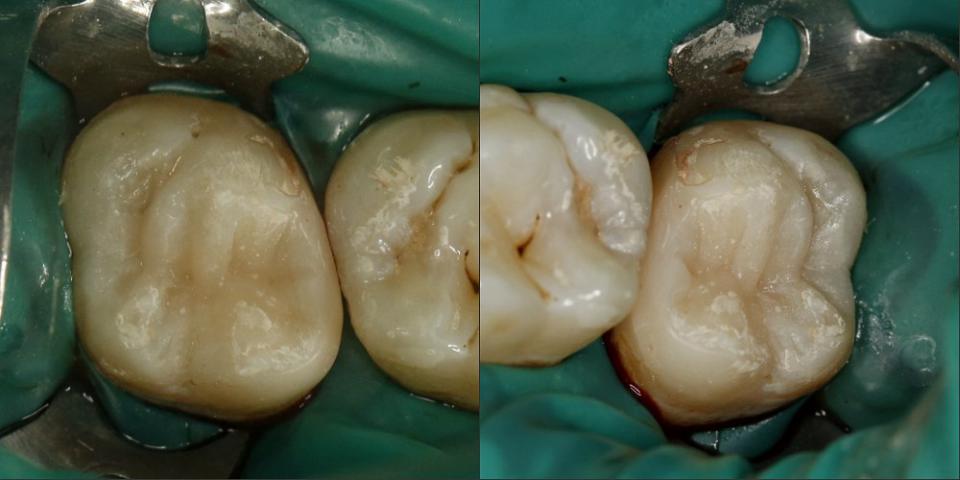

paraschyk1 Опубликовано 16 октября, 2015 Автор Опубликовано 16 октября, 2015 Это где ставят по 200гр?))бор нормальный стоит только гривен 40,а еще сам материал,полиры,паста полировочная,протравка,бонд, ершики для бонда,матрицца и матрицадержатель,анестетик,иголки доя карпульного шприца, ретракционная нить.Пачка перчаток 50 пар уже за 150гр перевалила,салфетки. А еще переодически новые наконечники надо покупать...Антисептики для рук и инструмента стоят дохера..А еще долгосрочные-амортизация ремонт установки, новые инструменты(пакеры,гладилки,зеркала...)А еще аренда(платный план) на который тоже идет свой материал(от 10 ки)... Вижу в теме. Ты забыл время. Время самое ценное. А пакеры и ершики копейки. Увы,но в Киеве еще можно поставить пломбы аля лепнина,за 200 грн. Но и срок им мал и вид соответствующий Но вот такую работу делать за 200грн я не буду,ну разве корешу.

paraschyk1 Опубликовано 16 октября, 2015 Автор Опубликовано 16 октября, 2015 Выпал недавно реставрированный жевательный семерка вместе со штифтами. Т.е. там остались одни корни, над десной ничего от зуба нет. Было 2 штифта, реставрация + обычная простая коронка сверху. Все это аккуратно выпало. Один стоматолог говорит, что даже браться не будет, мол через годик снова отвалится, только вырывать. Другой говорит, что здоровый корень, какой нафиг рвать, только делать. Ниже вариант спасения зуба,когда полная жопа. Такой зуб может бегать пять лет и более.

paraschyk1 Опубликовано 13 декабря, 2015 Автор Опубликовано 13 декабря, 2015 Починил форумчанена после неудачного лечения.